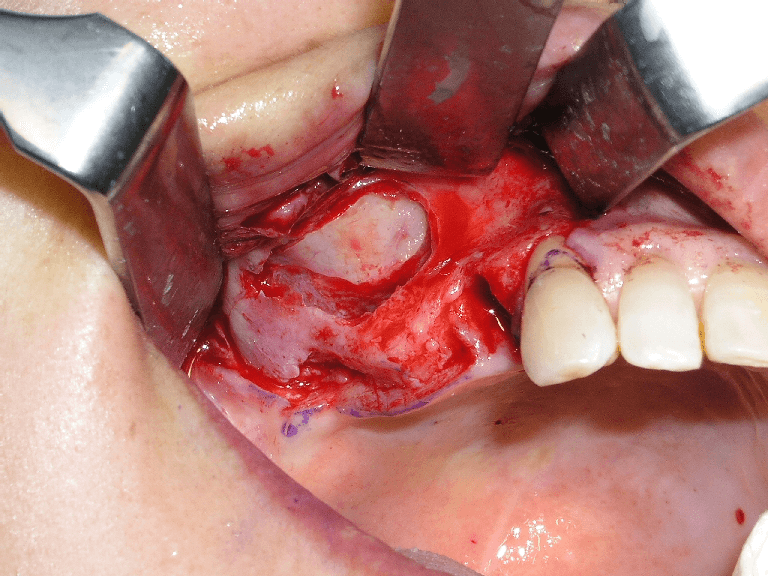

1983年に東京歯科大学が日本で最初にオッセオインテグレーテッドインプラントの概念とその治療法を紹介して以来、口腔インプラント療法は急速な進歩を遂げ、現在では、咀嚼障害や審美障害の改善手段として、長期間にわたる良好な治療成績が確認されています。千葉歯科医療センター口腔インプラント科では、近年、ますます複雑、多様化する患者様のニーズに応えるため、最新の設備や充実したスタッフを配備し、安心・快適・便利を実感できる診療科をめざしています。また、インプラント埋入手術時の鎮静法の併用、基礎疾患を持っている患者様の全身管理下での処置、骨移植、口腔内軟組織移植等の関連手術を行う設備体制を整え、大学医療機関の特色と利点を最大限に生かした治療を心がけています。

1~2本と歯の欠損が少ない場合でのインプラント治療は、従来の治療法(ブリッジや入れ歯)と比較して両隣の歯を削ったりする必要がなく、残っている歯に負担をかけないですみます。また、前歯の治療においては隣在歯と調和のとれた高い審美回復が必要とされることから、骨と粘膜の高度なマネージメントが必要とされます。口腔インプラント科では、高いレベルの審美修復治療の結果を達成するよう専門スタッフが対応しています。

部分入れ歯や総入れ歯などを使う必要がある歯の欠損に対するインプラント治療では、入れ歯と比較して違和感が少なく、咀嚼や発音などの機能回復が期待できます。また、欠如部以外の残存歯の治療が必要になる場合も、初診時からメンテナンスに至るまで一貫した包括的治療を行っています。また、インプラント埋入部位の骨が不足していたり、その他の要因でインプラント療法を断念されていた患者様に対しても、各分野の専門スタッフが高度な診断技術により対応をしています。